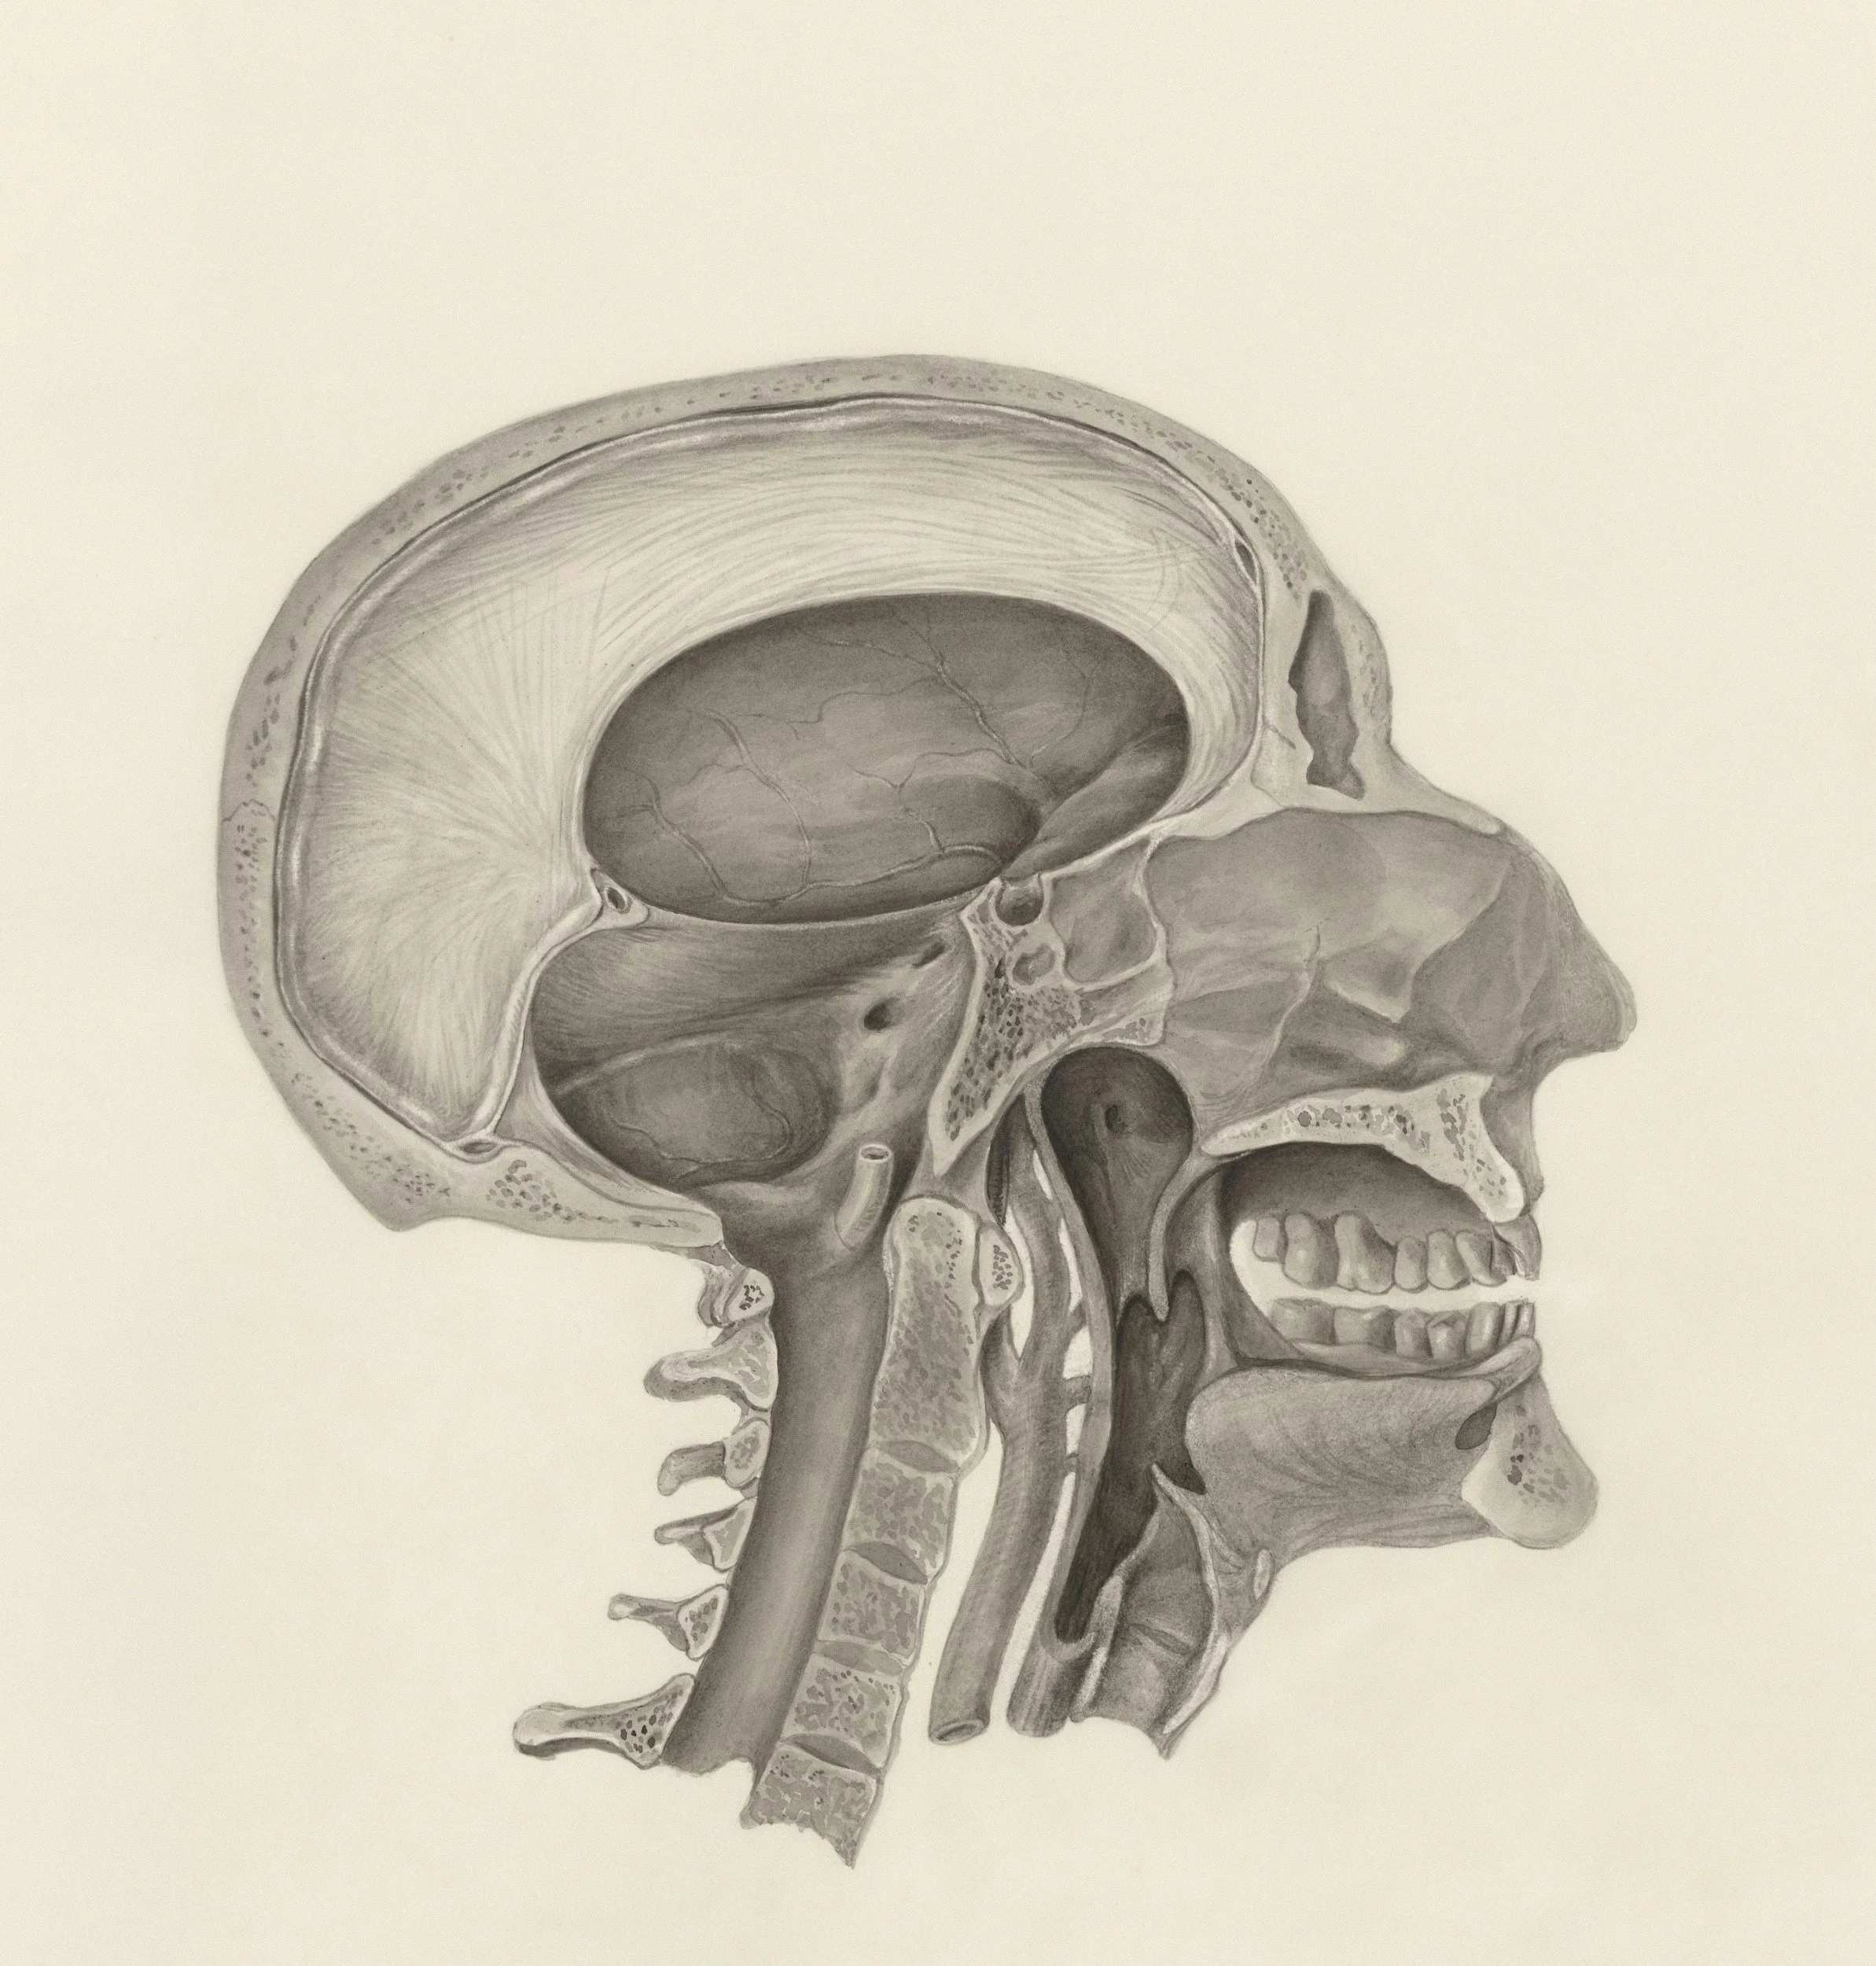

What Is TMJ Dysfunction?

TMJ (temporomandibular joint) dysfunction refers to issues affecting the jaw joint and surrounding muscles. This joint connects your jaw to your skull and plays a key role in speaking, chewing, and breathing.

When the joint or muscles are not functioning properly, it can lead to pain, tension, and restricted movement.